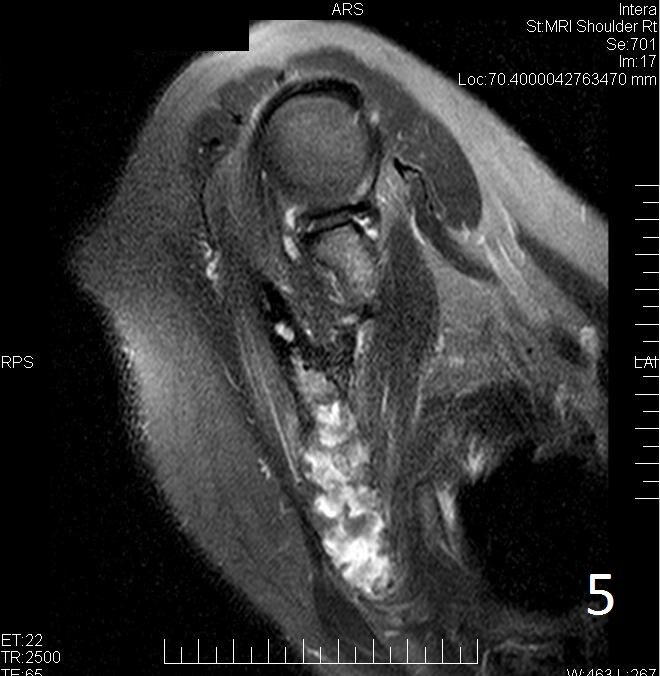

• Variable heterogeneous signal on T2 (Fig. 5)

Fig. 5. Same lesion on Axial T2W FS shows heterogenous signal.